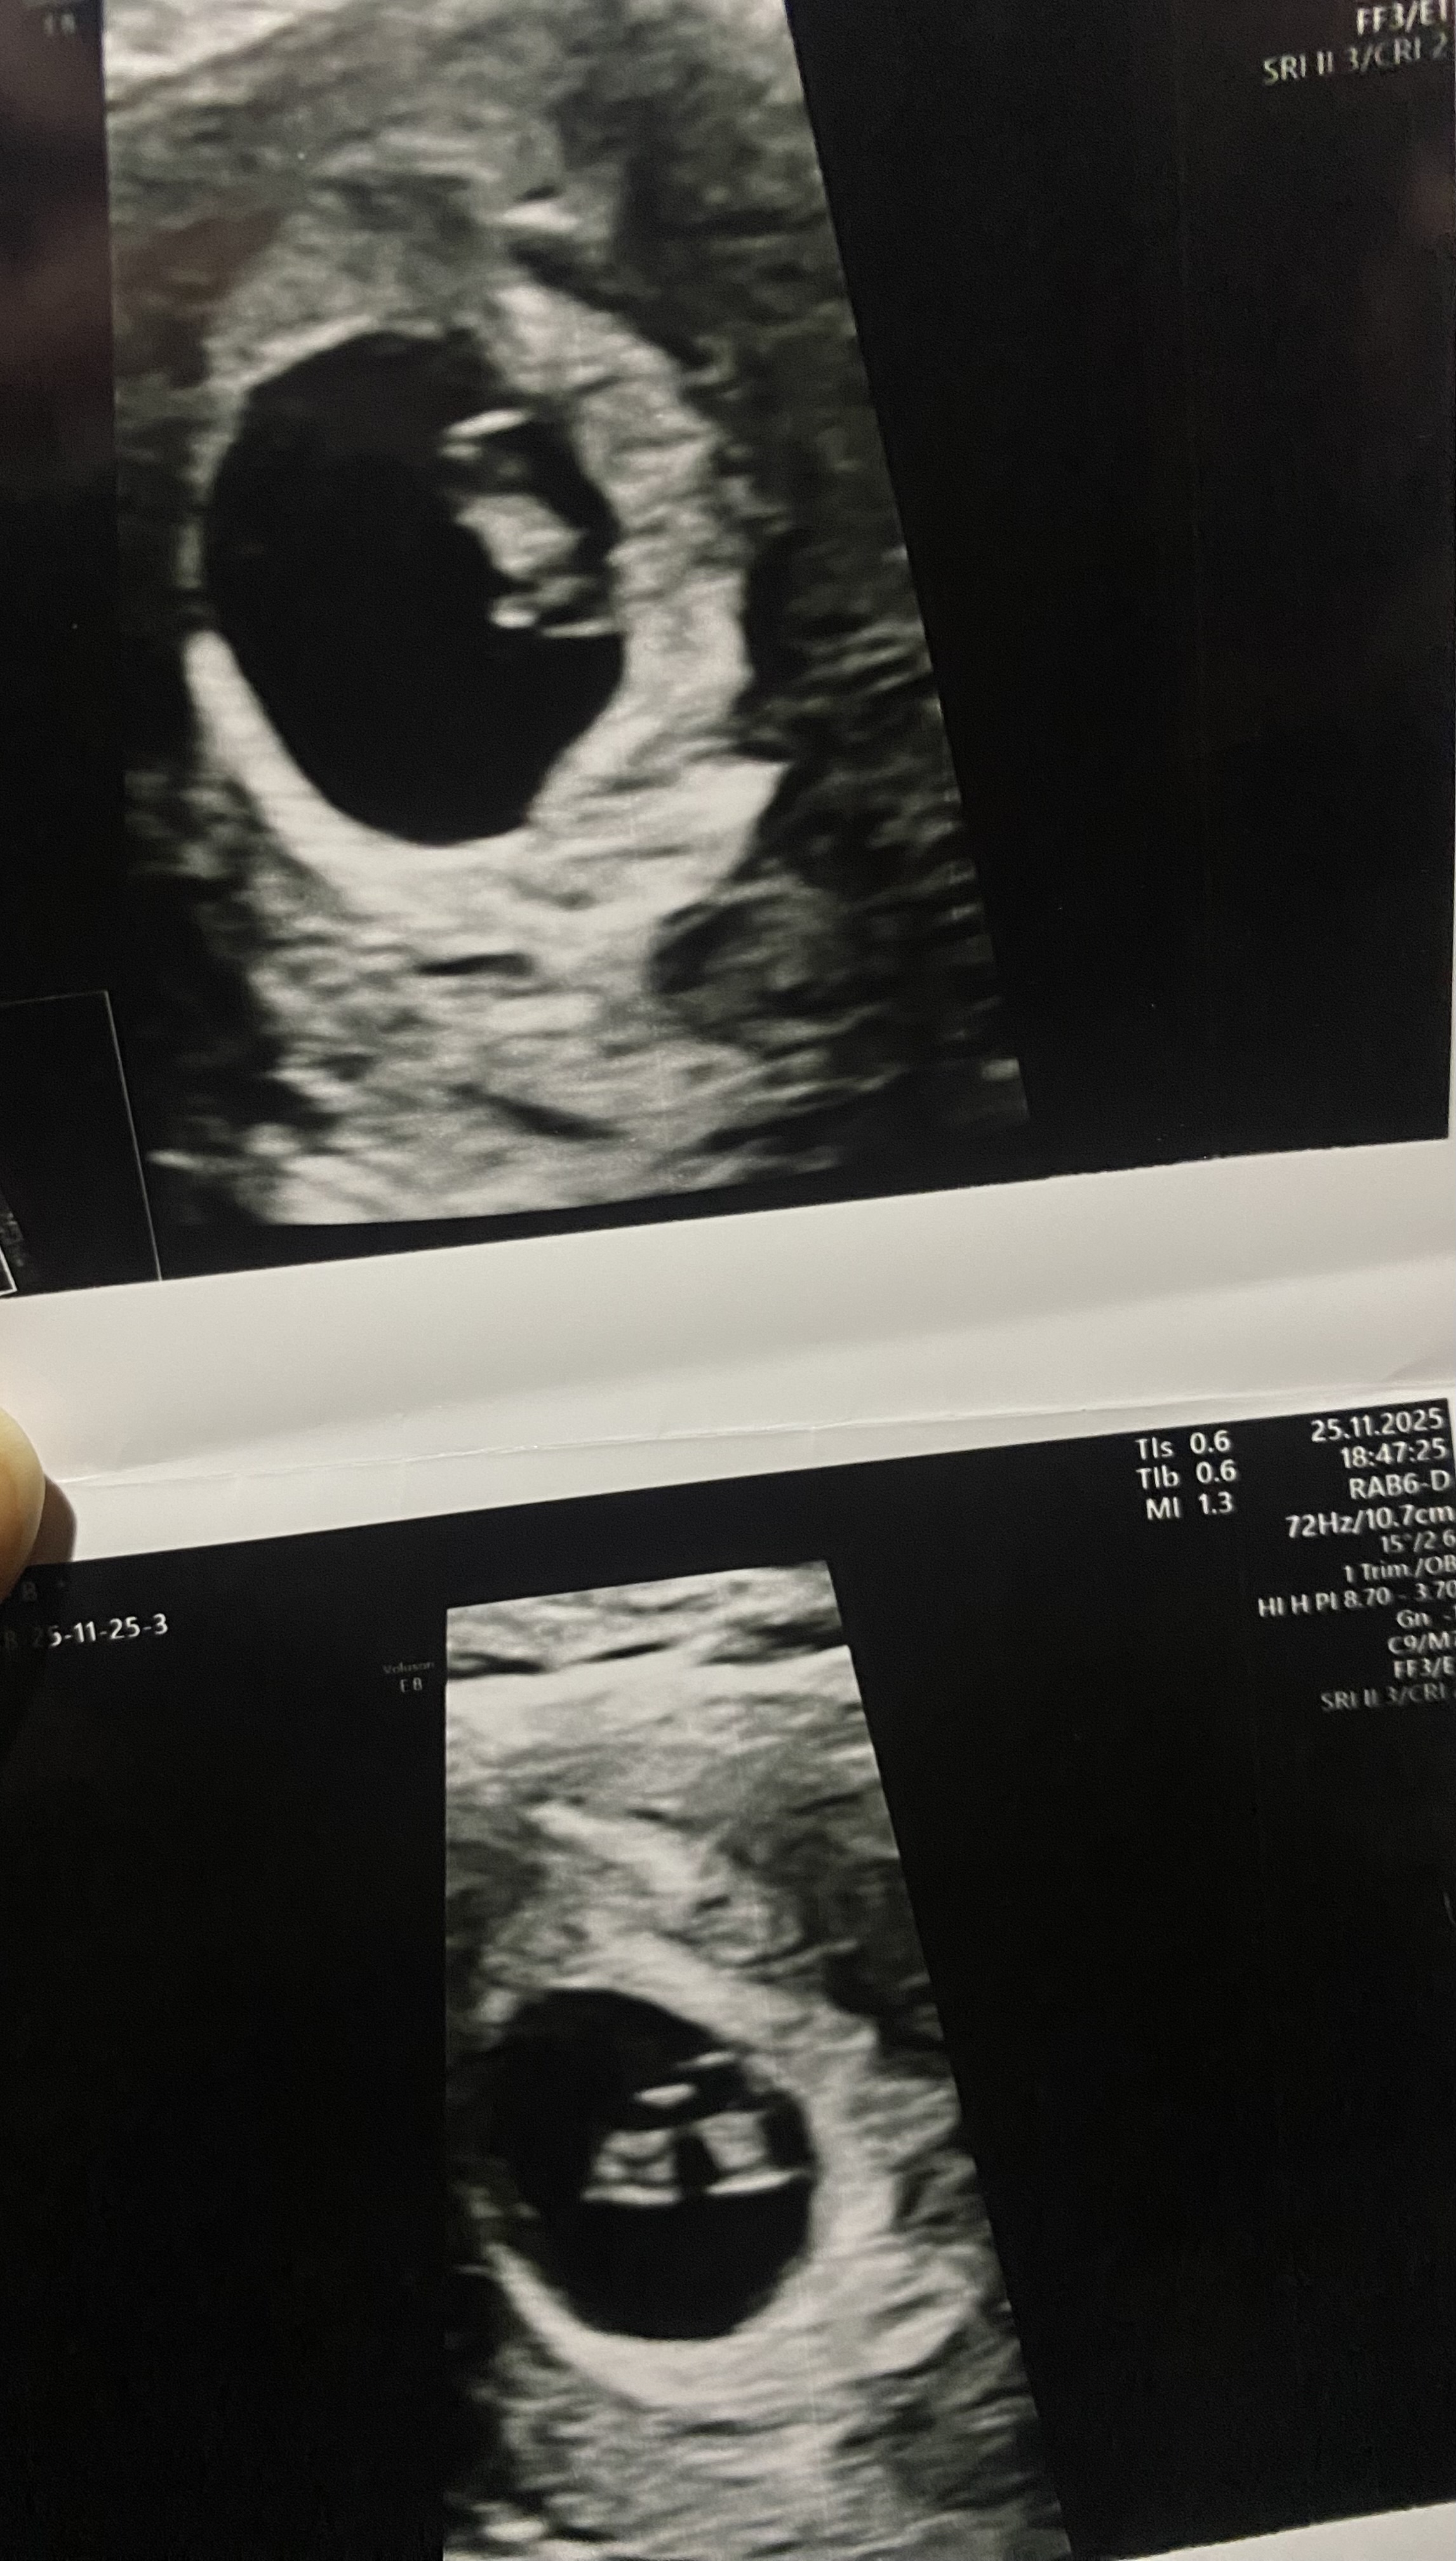

Da har vi vært på privat ultralyd, på den faste klinikken vi har gått privat til i alle svangerskapene. Vi fikk time til den jordmora som vi har vært oftest hos, og hun husket oss selv om det var noen år siden sist.

Mannen var ganske spak på venterommet, og det var mye tanker hos oss begge. Jeg fortalte at jeg hadde en dårlig magefølelse, og han sa at om det viste seg å stemme, så var det ikke slik at han ble glad for det. Men det er fortsatt mange tanker og følelser og bekymringer.

Hun vi var hos er utrolig dyktig og hyggelig, og vi snakket litt om situasjonen før ultralyden. Fikk velge om vi ville se skjermen eller ikke, men vi ville begge se uansett resultat. Og der var det en liten bønne med bankende hjerte målt til 9mm. :Heartred

I følge målingen er jeg da 7 uker og noen dager på vei i stedet for 6+6. Hjerteslagene ble målt til 150 eller 160 (husker ikke helt), men uansett godt over den grensen de burde ligge på på dette tidspunktet. Alt er jo så smått og tidlig ennå, men det så i alle fall helt normalt ut så langt. Riktig plasser - og kun ett foster. Hadde det vært tvillinger, i denne situasjonen, så tror jeg vi hadde gått i gulvet begge to. :dead:

Nå må vi bare få satt oss ned hjemme og snakke og ta det derfra. Det er godt å vite at alt ser bra ut så langt i alle fall, selv om det fortsatt da er slik at vi må lande på et valg etter hvert. Men for meg hadde det vært helt forferdelig om vi hadde fått dårlig nytt, selv om det ville vært «enklere» sånn sett.